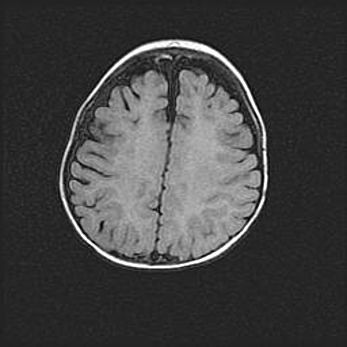

Наружная гидроцефалия с возможной атрофией височных областей.

Возраст: 28 дней

Вес: 3670 г

Пол: мужской

Окружность головы: 38 см

Срок гестации: 40 недель

Гидроцефалия головного мозга у новорожденных – это заболевание, которое характеризуется скоплением избыточного количества спинномозговой жидкости в желудочковой системе головного мозга в результате затруднения её перемещения от места выработки к месту поглощения в кровеносную систему или вследствие нарушения абсорбции. При открытой наружной форме гидроцефалии у новорожденных расширяются и переполняются субарахноидные пространства.

При нормотензивных  формах,  которые,  как  правило,  являются  следствием  перенесенных ишемических  повреждений  паренхимы  мозга,  возможно  сочетание микроцефалии  с нормотензивной гидроцефалией. В основе данных изменений лежит атрофия больших полушарий с преимущественной  локализацией  в  лобно-височных  областях.